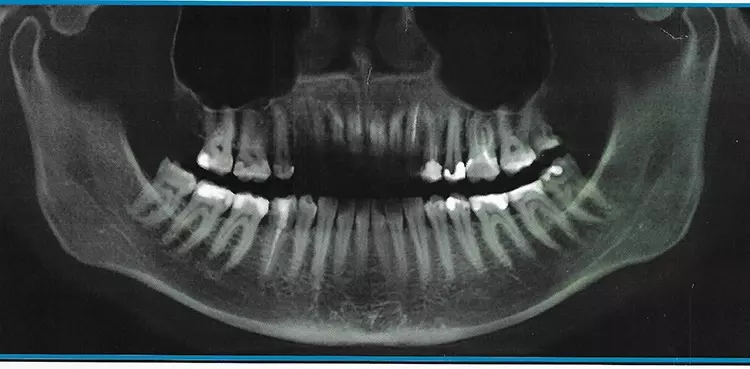

Abb. 1: Natürlicher Gebisszustand der Patientin vor Erstvorstellung. SDS

Abb. 1: Natürlicher Gebisszustand der Patientin vor Erstvorstellung.

Die hier vorgestellte 37-jährige Patientin litt bereits seit langer Zeit unter chronisch lokalen sowie undefinierbaren systemischen Schmerzen, was gemäß Angaben diverser Vorbehandler der Patientin funktionell durch ihren Fehlbiss bedingt sei. Regelmäßige Einschleifmaßnahmen hatten bis dahin keine Besserung der Symptomatik zur Folge. Im Jahr 2019 war der generelle Leidensdruck, der laut damaliger Einschätzung von der Mundhöhle ausging, so groß, dass alio loco ein Großteil der natürlichen und wurzelkanalbehandelten Zähne schrittweise extrahiert wurde (Abb. 1).